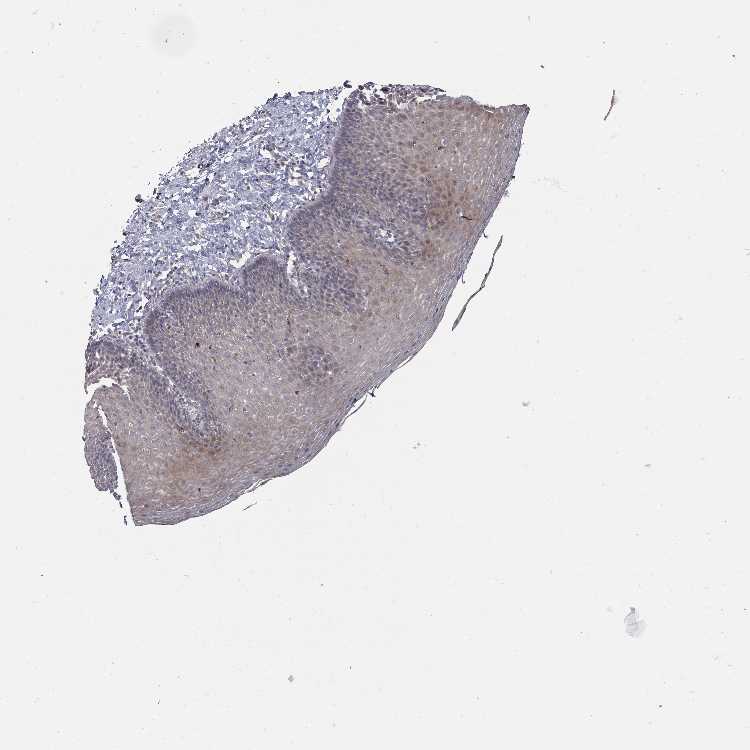

ESOPHAGUS - Antibody stainingi

Antibody staining in the annotated cell types in the current human tissue is reported as not detected, low, medium, or high, based on conventional immunohistochemistry profiling in selected tissues. This score is based on the combination of the staining intensity and fraction of stained cells.

Each image is clickable and will lead to virtual microscopy that enables deeper exploration of all samples and also displays staining intensity scores, fraction scores and subcellular localization as well as patient and tissue information for each sample.

Antibody HPA051411

Squamous epithelial cells Low